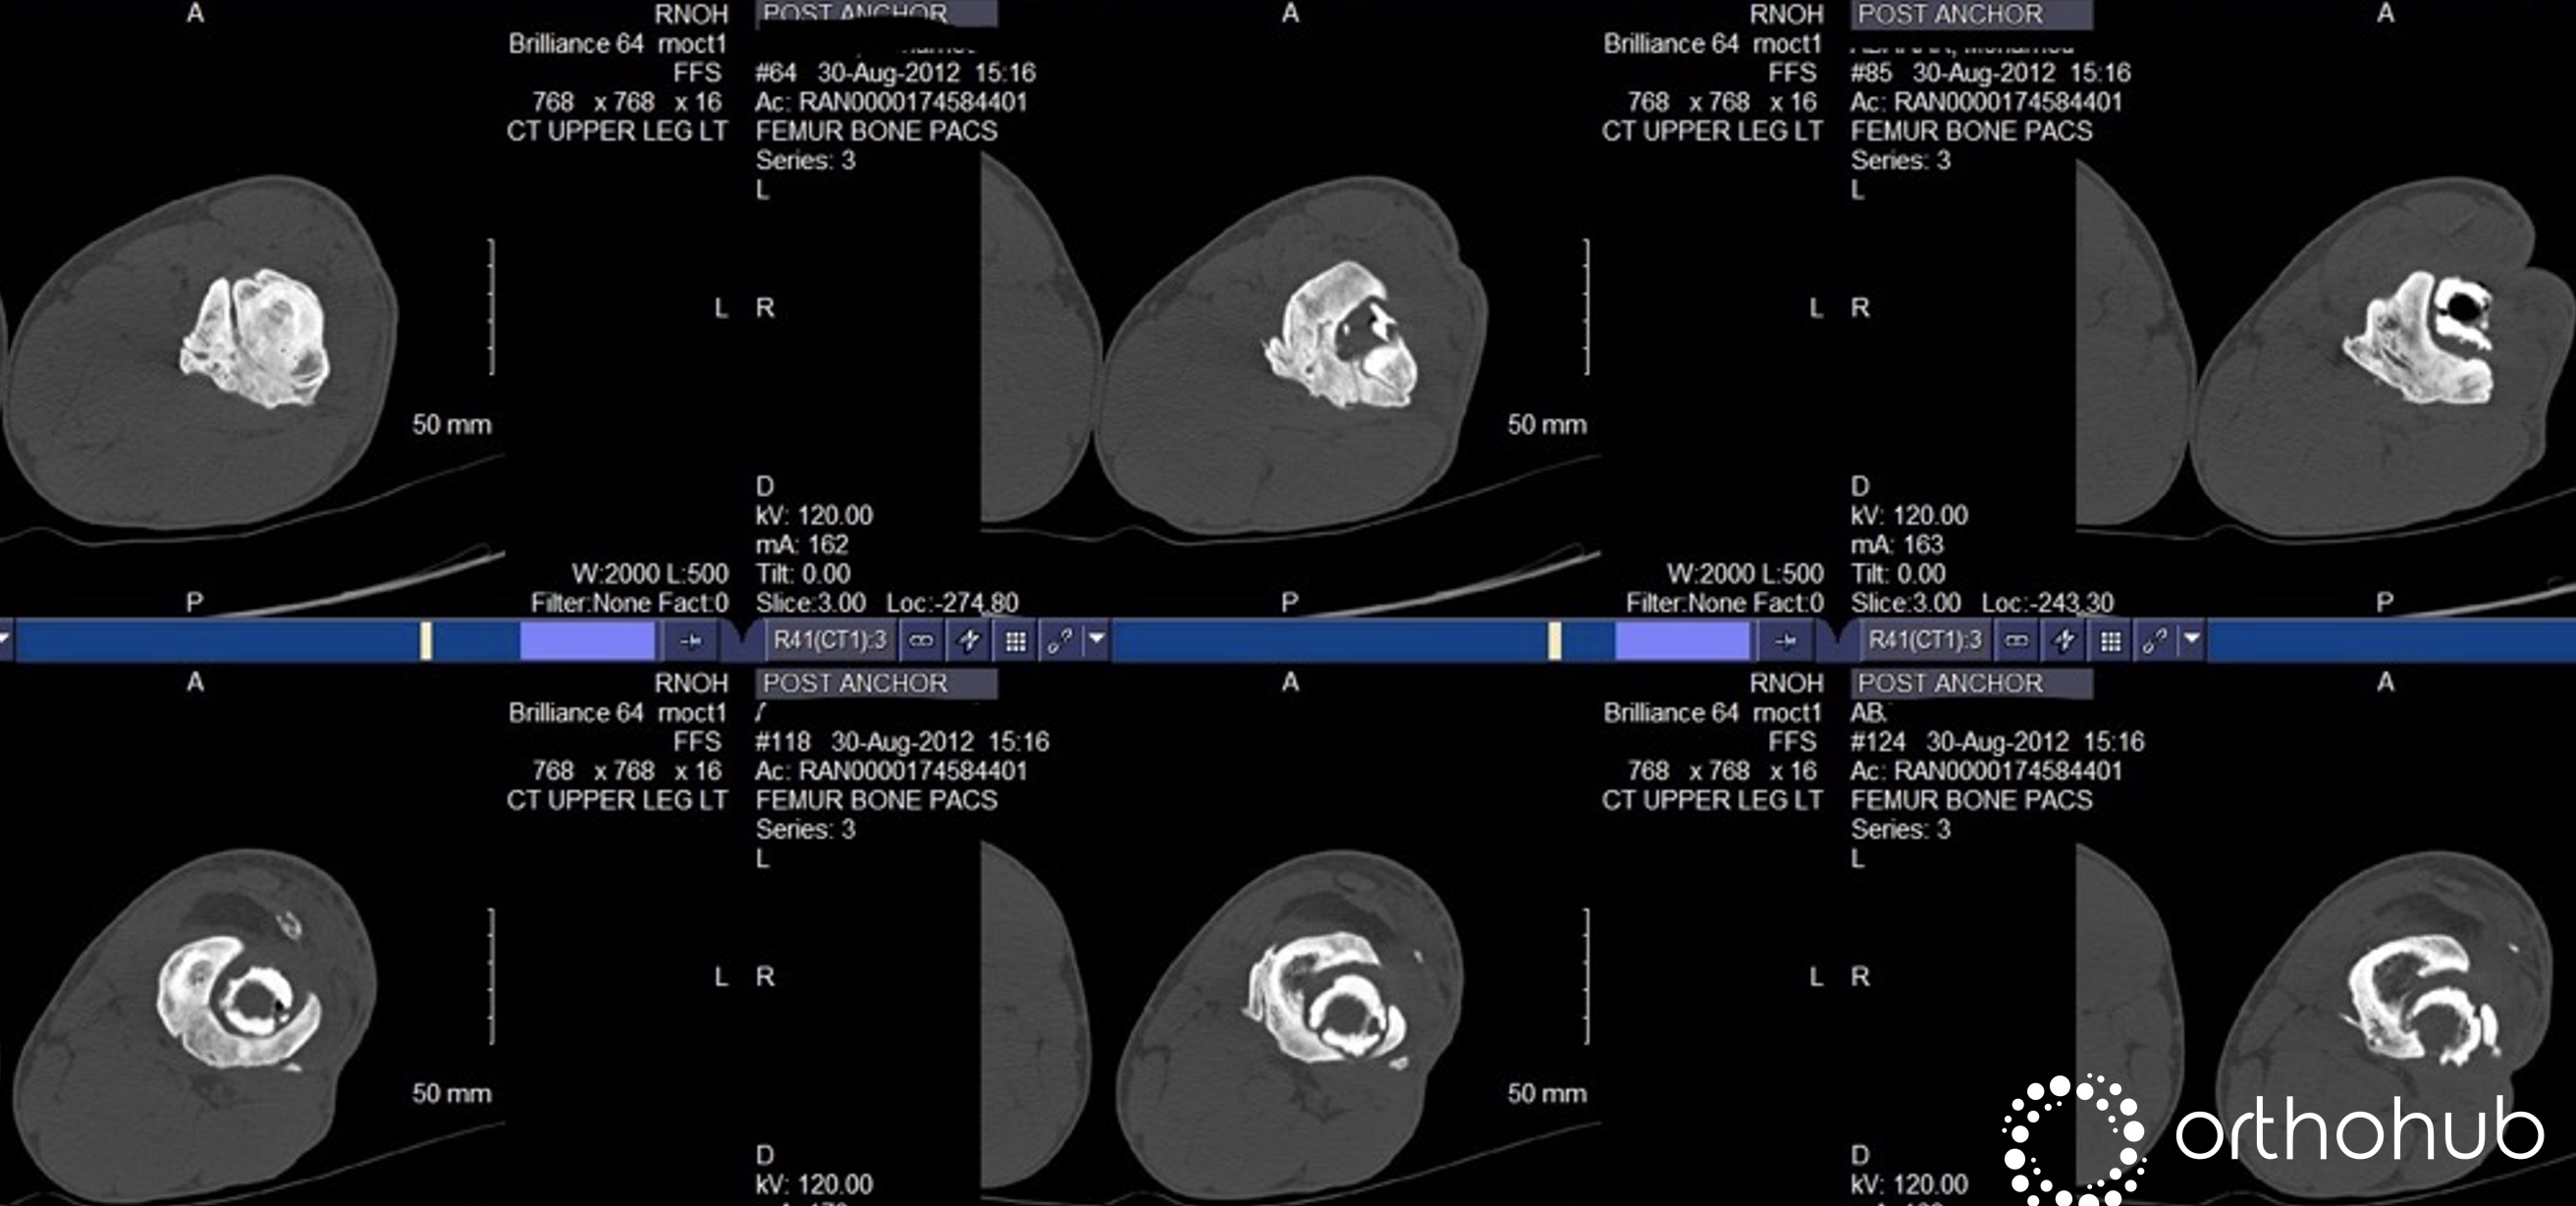

60 y.o. Male, falls from a ladder. Bilateral closed Pilons (this case concerns the right side). Placed into a spanning external fixator and achieved a nice reduction.

The patient got ORIF with plates. The post-op reduction looked decent and no infection. However, at 8-months the medial fixation started to fail. The patient was weight bearing with discomfort, needing crutches and a boot still.

Updated position: The treating surgeons decided to revise the medial fixation and that worked nicely for a while, until the new medial plate/screws broke again! At 29-months the pt was still on crutches and in pain, albeit a little improved (image A). A CT seemed to show that the fracture was healed and so the hardware was taken out (image B). 1-week later, a wt-bearing x-ray clearly showed a varus non-union (image C). See also CTSo, the situation is a varus non-union. Reasonable soft tissues (will tolerate further open surgery). Never been overtly infected.